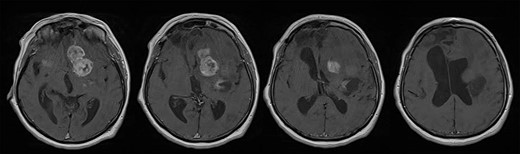

A 65-year-old female patient was presented with progressive drowsiness, cognitive slowing, poor mobility and incontinent. In addition, the patient had sensorimotor dysphagia and right-sided hemiparesis. Initial computerized tomography (CT) and magnetic resonance imaging (MRI) brain scans revealed an irregular expansive multicenter process located in the basal ganglia, frontobasal and in the area of the frontal operculum left and frontotemporal right with extensive vasogenic edema of the left frontal and parietal lobe and a compressive effect on the left lateral and III ventricle. After the administration of intravenous contrast, the process showed heterogeneous enhancement (Fig. 1). Ventricular system was dilated with a sign of transependymal edema.

Brain MRI scans revealed an irregular expansive multicenter process located in the basal ganglia, frontobasal and in the area of the frontal operculum left and frontotemporal right with extensive vasogenic edema of the left frontal and parietal lobe and a compressive effect on the left lateral and III ventricle; after the administration of intravenous contrast, the process showed heterogeneous enhancement. Ventricular system was dilated with sign of transependymal edema.